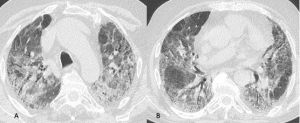

Figura 11: Uomo di 68 anni giunge in Pronto Soccorso per grave dispnea, IRA e febbre, esegue TC TORACE all’ingresso nel sospetto di polmonite da SARS-CoV-2. La TCAR (scansioni assiali A-B-C-D) documenta ispessimento liscio dei setti interlobulari in entrambi i polmoni più evidente in sede perilare e nei lobi inferiori ove si associa la presenza di alcune aree di aumentata densità con aspetto a "vetro smerigliato" maggiori a destra. Si associa falda di versamento pleurico bilaterale. L’ipotesi diagnostica formulata ed in seguito clinicamente confermata è stata quella di alterazioni di natura emodinamica.

Figura 12: Donna di 70 anni affetta da tumore al polmone in trattamento con un inibitore della tirosin-chinasi. Trascorsi 15 giorni dall’inizio della terapia la paziente lamenta sempre maggiori difficoltà respiratorie e tosse. Alla TC di controllo (scansioni assiali A-B-C-D) si rileva "vetro smerigliato" diffuso in entrambi i polmoni ed ispessimento liscio di alcuni setti interlobulari. Si giunge alla diagnosi di pneumpatia indotta da farmaci dopo aver escluso le ipotesi di edema cardiogeno e di infezione polmonare.